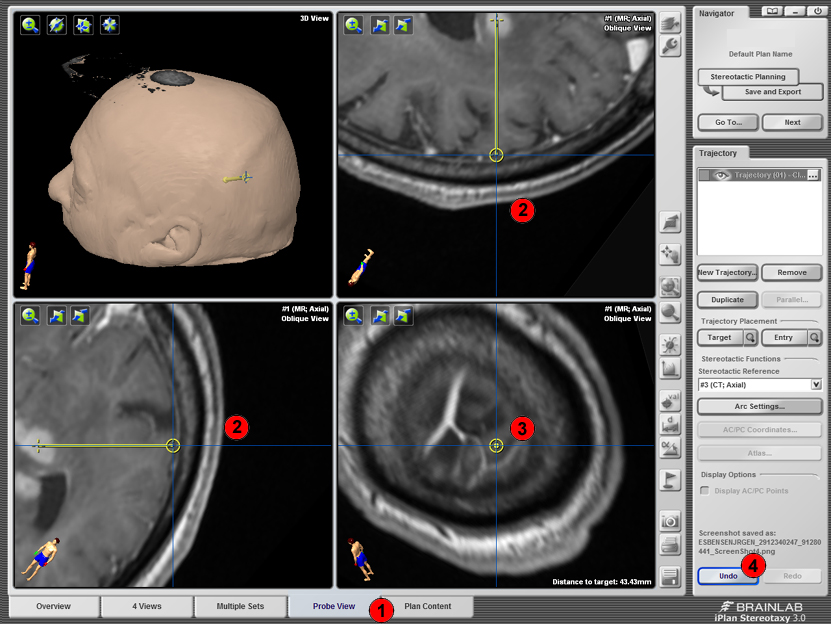

Probe view

Target bør chekkes på både CT og MR. I MR serien kan man vælge Probe View (1). Her kan man vælge enterypoint så trajectory går perpendikulært på kraniet så boret ikke skrider (2), og man kan scrolle gennem snittene i probe view og sikre at man går mellem corticale kar (3) og hvis det er en scanning uden kontrast kan man vælge toppen af en gyrus. Ved fejlklik kan Undo-knappen anvendes (4).